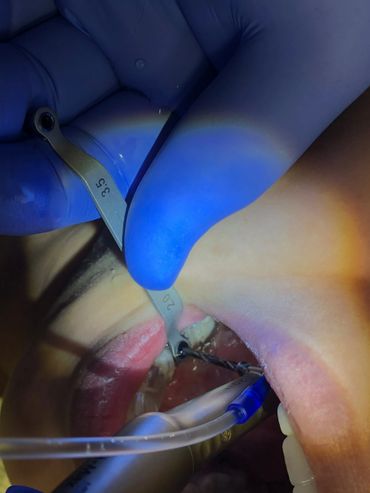

The Neodent® EasyGuide Sleeve is selected according to mesiodistal space and implant diameter.

During digital planning, sleeve positions must be assessed to avoid impact

Neodent® EasyGuide offers two sleeve diameters for optimizing positioning

The Neodent GM Guided Surgery Kit is a compact, easy to use guided surgery system. Clinicians can provide CT scan, digital photos, and impressions to a laboratory for precise implant guide fabrication. Temporary teeth can be made and the lab will know the depth, angle, and timing of the connection of the implant. This allows you better esthetics and provides the patient teeth the same day with less chair time.